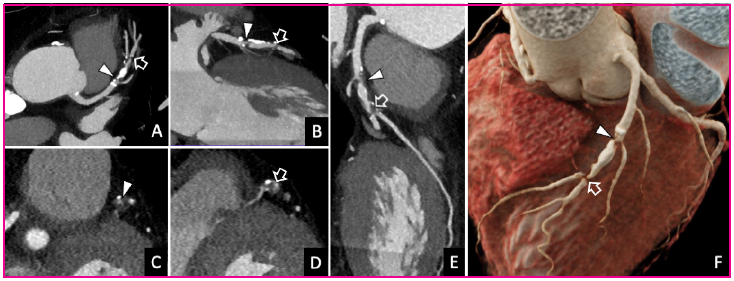

Fig. 1 Coronariografía-TC. A, B: Reconstrucciones multiplanares de la arteria coronaria descendente anterior. C, D: Reconstrucciones perpendiculares al eje largo del vaso. E. Reconstrucción planar curva. F. Reconstrucción volumétrica cinemática. El estudio demostró estenosis del 70-99 % en el tercio medio de la arteria coronaria descendente anterior, que engloba al origen de la primera (punta de flecha) y segunda rama diagonal (flecha hueca).